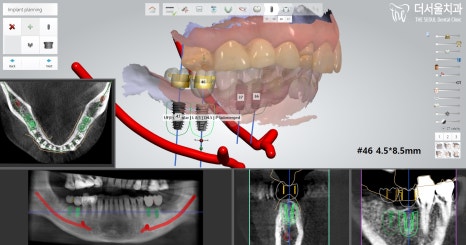

우선 문제되는 이를 발치 하고

👉컴퓨터 분석 프로그램을 이용하여

수술 계획을 수립했습니다.

40번 대는 크게 문제될 것이 없었는데,

30번 대는 염증으로 인한 골소실이 있어

식립에 있어 조금 더 신중을 기해야 될

필요가 있었습니다.

그치만 뼈이식을 할 필요는 없었기에

그리 어렵지 않게 진행할 수 있습니다.